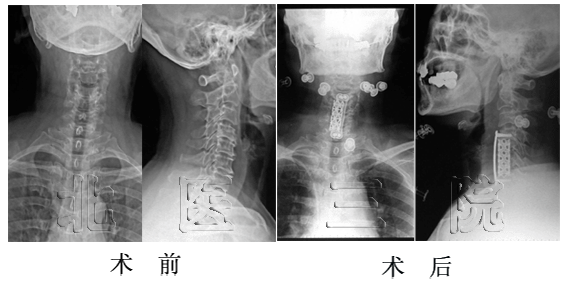

脊髓型颈椎病:前路椎体次全切,椎间钛网植入钛板内固定